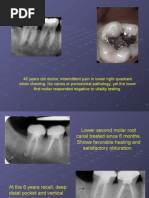

FIGURE 1 – Radiographic progression of healing in horizontal root fracture cases with different types of healing. This

figure showcases preoperative (A ), postoperative (B ), and follow-up radiographs (C ) of 4 teeth with HRF. The type of

healing is classified according to Andreasen and Hjorting-Hansen’s19 classification, 1) Case 1 (tooth 1.1): Healing with

calcified tissue, fragments in close contact, and minimal or no visible fracture line (type I). 2) Case 2 (tooth 1.1): Healing

Data Collection with interproximal connective tissue, fragments appear separated by a narrow radiolucent line, and fractured edges

A standardized data collection form was appear rounded (type II). 3) Case 3 (tooth 2.1): Healing with interproximal bone and connective tissue, fragments

completed in Microsoft Excel 2016 for each separated by a distinct bony bridge (type III). 4) Case 4 (teeth 1.1 and 2.1): Nonhealing with interposition of granulation

patient and included the following information. tissue, evidenced by widened space between fragments or radiolucency adjacent to the fracture line (type IV).